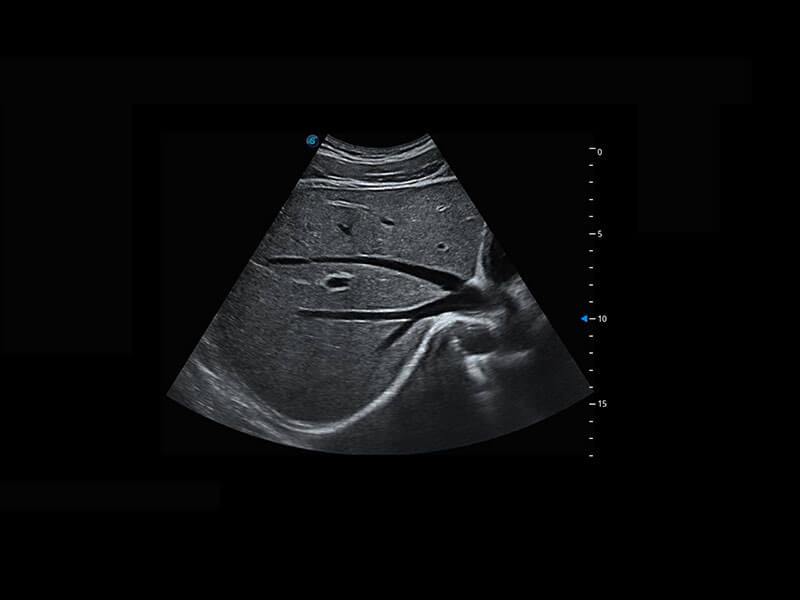

P60优异的图像质量搭载专科探头,在妇科基础疾病的诊断、卵泡生长的监测、输卵管通畅情况的判别等方面为您提供生殖应用方案。

腔内妇科-宫腔分离